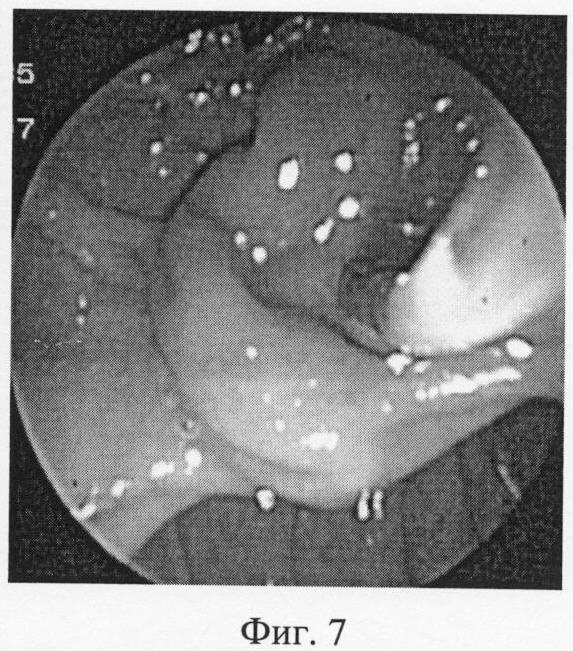

Фиг.7 – глубокая канюляция и получение холангиограммы не удается.